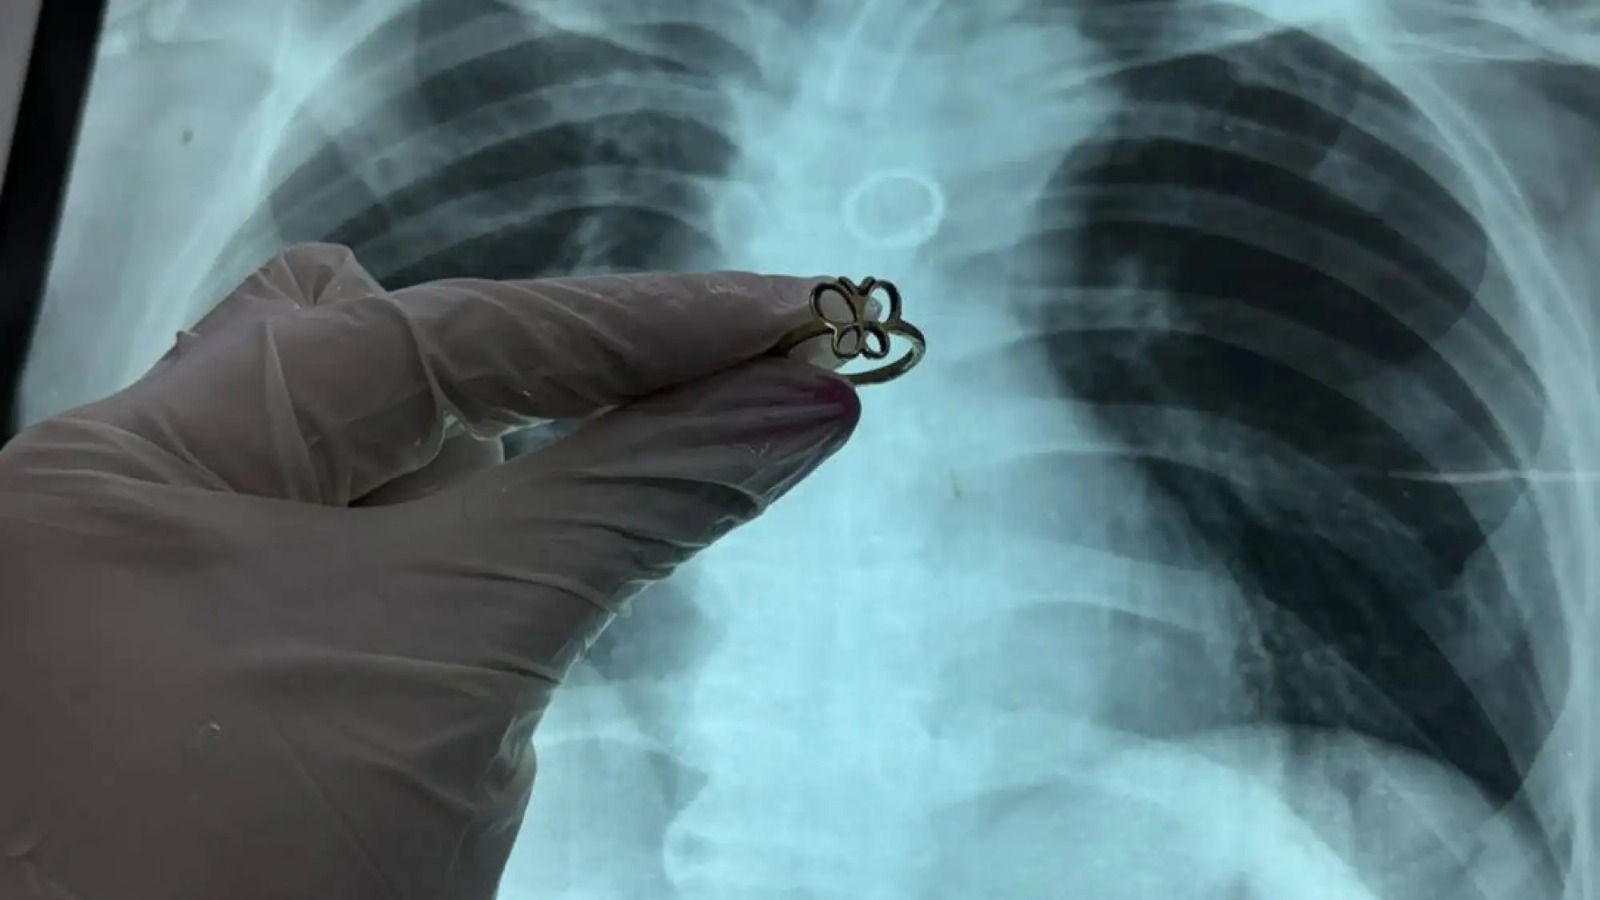

Un hecho inusual se registró en el Instituto Nacional de Enfermedades Respiratorias y del Ambiente Prof. Dr. Juan Max Boettner (Ineram), donde un paciente de 54 años acudió para realizarse estudios tras un accidente de motocicleta y, durante las radiografías, los médicos detectaron un anillo de oro alojado en uno de sus pulmones.

El hallazgo fue confirmado por el doctor Carlos Morínigo, quien explicó que el objeto, con forma de mariposa, fue visualizado inicialmente en una placa de tórax como una figura redondeada ubicada en el bronquio. Posteriormente, mediante un procedimiento de exploración de las vías respiratorias, se logró extraer el anillo.

Morínigo destacó que el material del objeto evitó consecuencias más graves. “Por suerte era de oro, ya que otros metales pueden oxidarse rápidamente en contacto con la mucosa, generando lesiones, fisuras e infecciones severas en los bronquios”, explicó.

El médico indicó que aún se desconoce cómo el anillo llegó hasta el pulmón del paciente, calificando el episodio como un hallazgo inusual.